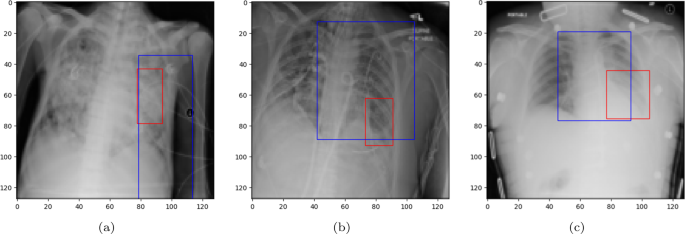

A bounding box (BBOX) is a rectangular region that is commonly used to localize (highlight) the interest area. Figure 8 illustrates the BBOX of some pneumonia disease instances predicted by the proposed ECGL model. The red box refers to the ground truth BBOX stated for the X-ray image, and the blue box demonstrates the predicted box by the ECGL model. It is important to note that the Base model cannot generate BBOX due to the lack of explanation constraints required for BBOX prediction.

Looking at Fig. 8(a) and 8(b), it is evident that the proposed ECGL correctly predicted the BBOX, aligning with the true box, even though the model estimated a larger area. This points out that considering the BBOX constraints in the model as integrated explanation constraints is effective in highlighting the attention to more relevant regions. Figure 8(c) presents a case where the predicted BBOX is partially within the lung area and may highlight the need for more refined BBOX constraints to better capture the spatial extent of pneumonia.